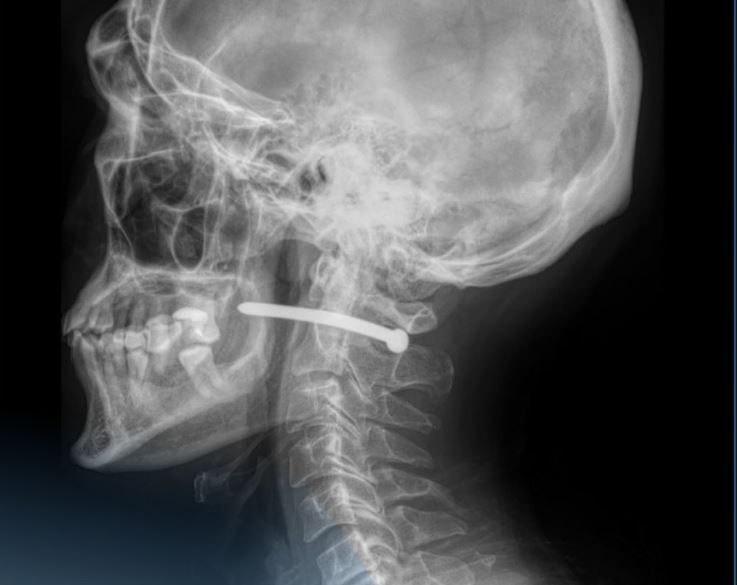

51-летний житель Петропавловска оказался в шаге от серьезной трагедии. Мужчина поступил в многопрофильную городскую больницу с необычной и крайне опасной травмой — гвоздем в заушной области, сообщает Qazaqstan Media.

Как выяснилось, во время ремонтных работ он случайно ранил себя строительным гвоздем из пневматического пистолета.

«Гвоздь прошел в непосредственной близости от шейного отдела позвоночника. Мужчине чудом повезло — жизненно важные структуры не были задеты», — сообщили в пресс-службе медучреждения.

Оперативное вмешательство провели челюстно-лицевые хирурги. Специалисты аккуратно удалили инородное тело, провели ревизию и обработку раны. После наложения швов и стерильной повязки пациента отпустили домой с необходимыми рекомендациями.